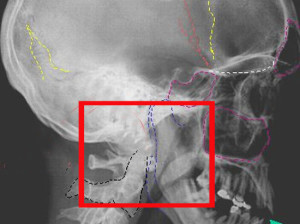

В больнице проводится комплексная диагностика: рентгенография, компьютерная и магнитно-резонансная томография. Также свое заключение делают офтальмолог, лор и невропатолог.